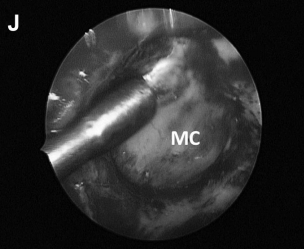

▼(G)切除病变后,术中可见内侧的后颅窝硬脑膜,外侧为Meckel腔(MC)和半月神经节。可用肌电图监测探头监测三叉神经的运动功能状态。

▼(L)使用鼻中隔瓣(NSF)完成封闭。CC,囊包膜;PFD,后颅窝硬脑膜;S,蝶鞍;T,肿瘤。